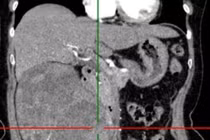

Loại bỏ khối u thận 1,2kg cho người bệnh 72 tuổi đau âm ỉ vùng lưng hông